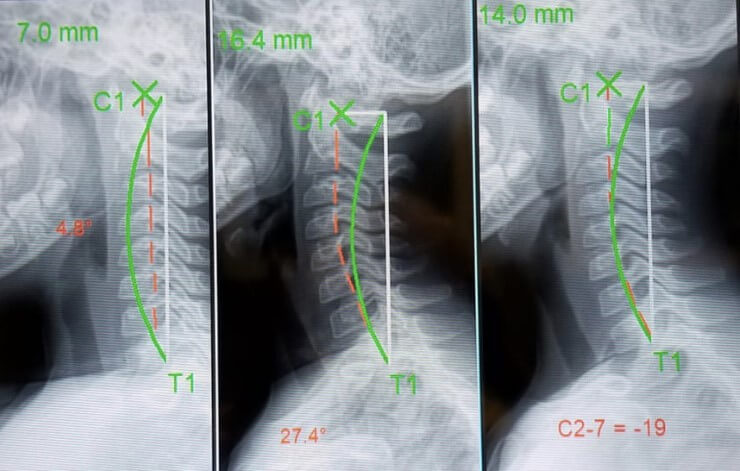

Digital X-Rays – Pinpointing misalignments and quantifying forward head posture.